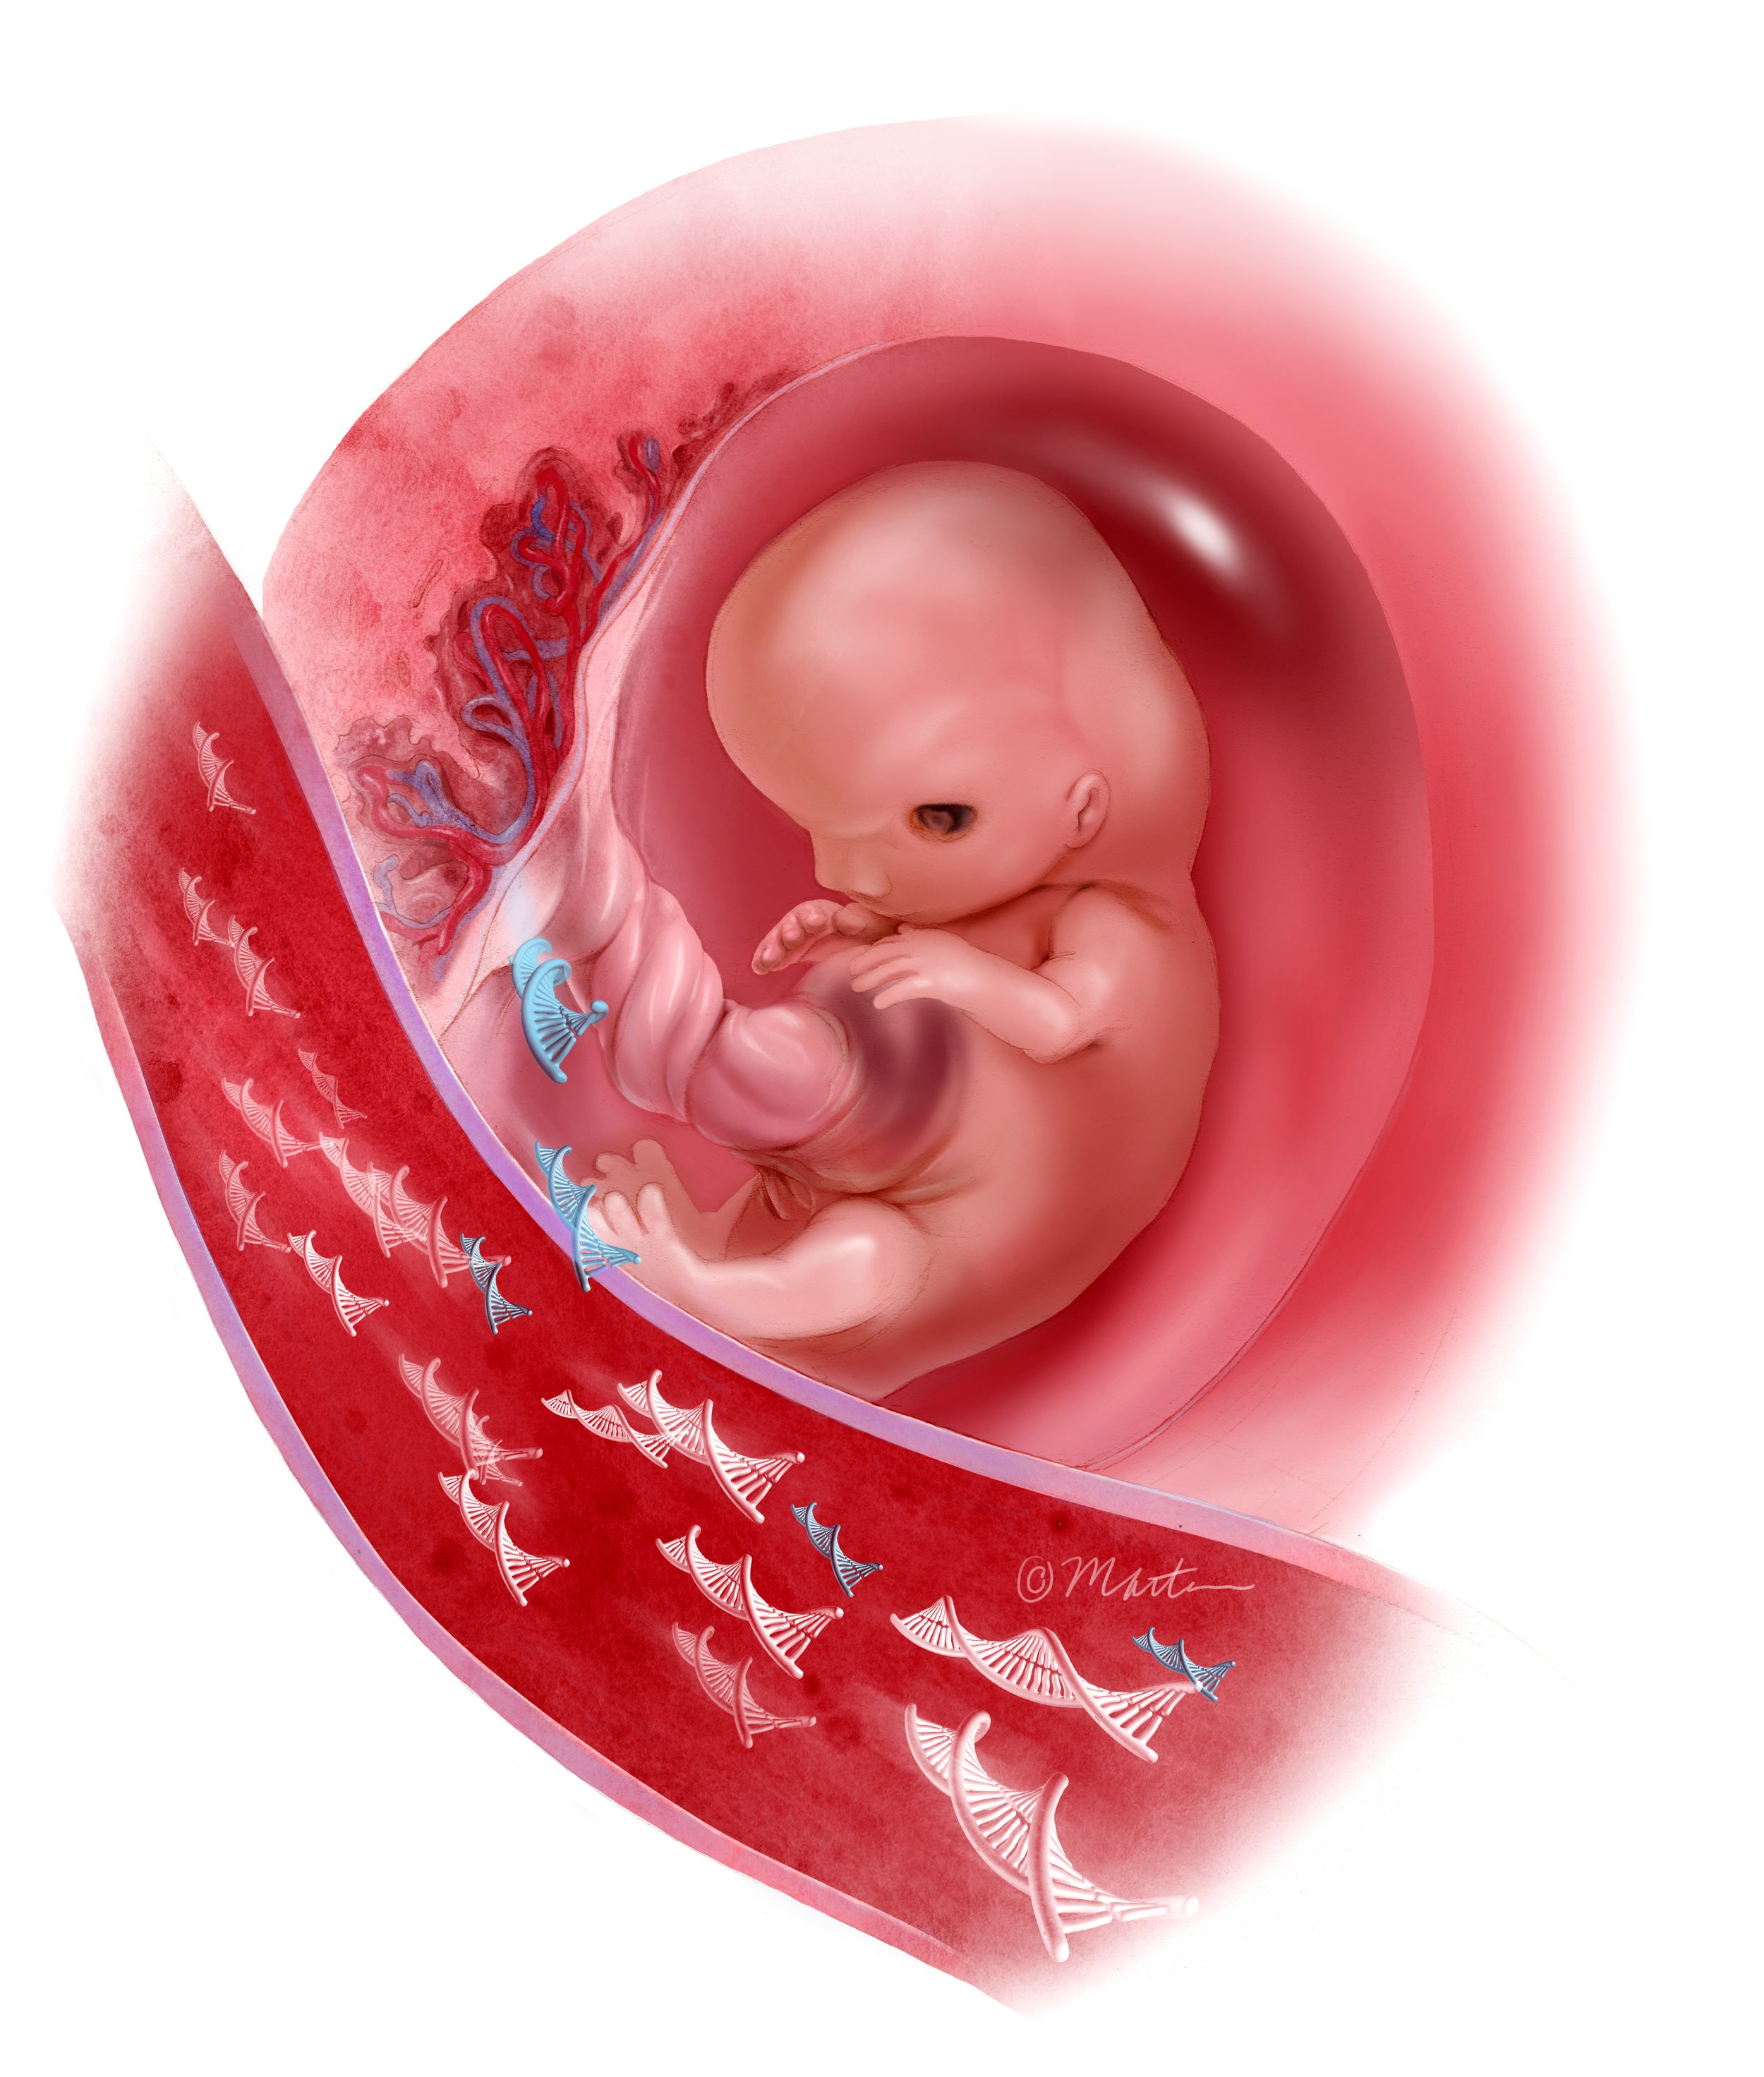

cfDNA Testing